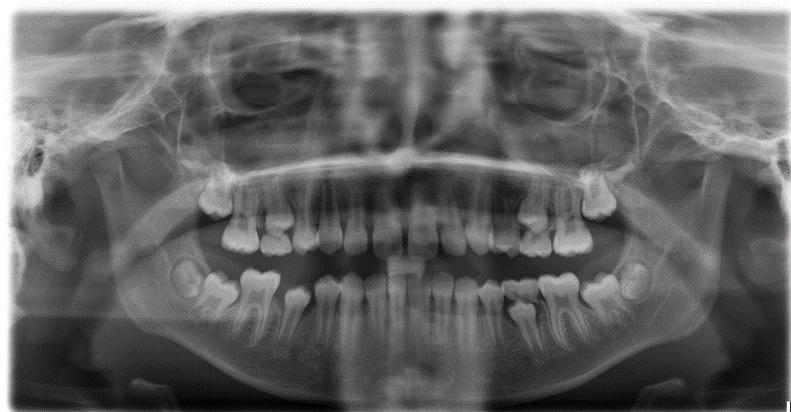

• studio delle radiografie del cranio (teleradiografia latero-laterale e tracciato cefalometrico e teleradiografia postero-anteriore) (Fig.4)

Fig. 4. teleradiografia latero laterale- tracciato cefalometrico-Teleradiografia postero-anteriore